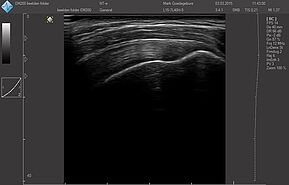

Области исследований:

- Брюшная полость

- Акушерство и гинекология

- Урология

- Щитовидная железа

- Молочная железа

- Кардиология

- Костно-мышечная система

- Педиатрия

- Нейросонография

- Исследование сосудов

- Транскраниальные исследования

Датчики имеют большую чувствительность и высокое разрешение, благодаря чему обеспечивают максимальное проникновение и улучшают соотношение сигнал /шум. В результате формируется максимально четкая детализированная картинка УЗИ изображения.